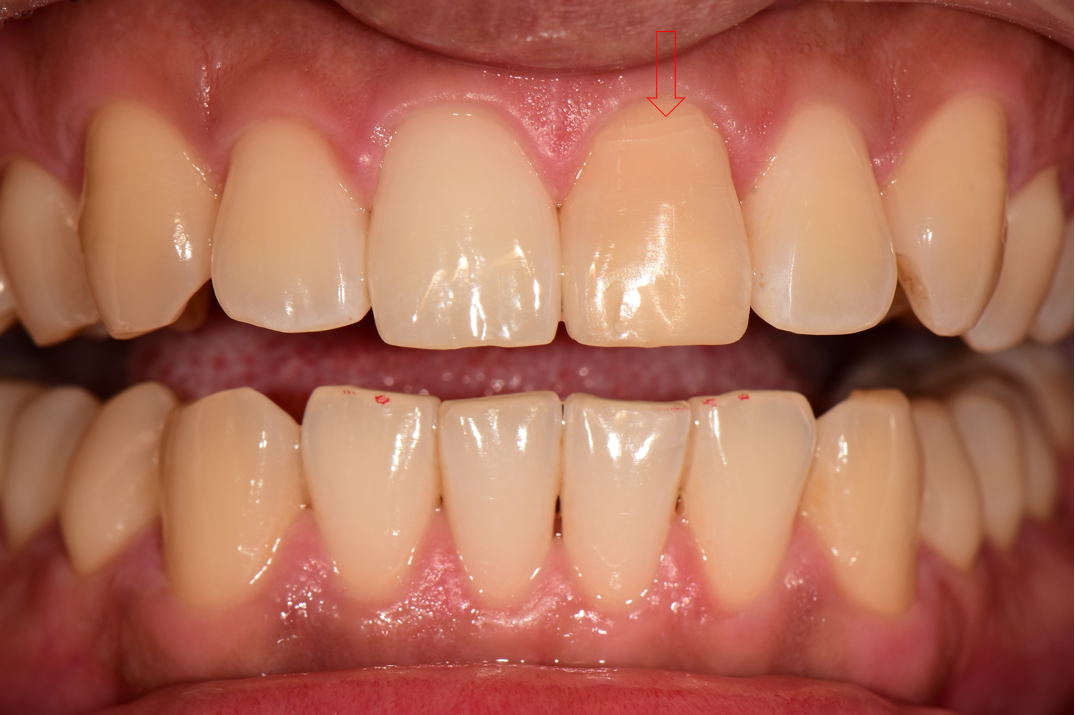

<처음 내원>

30대 남성분이 넘어져서 앞니가 금이 간 상태로 내원하셨습니다.

CT 검사 결과 치아의 머리 부분이 전부 부러져서 어쩔 수 없이 발치가 필요한 상황이었습니다.

<임플란트 식립>

발치 당일 임플란트를 식립 후 엑스레이 사진입니다.

수술 후 임시치아를 먼저 해드렸습니다. 당일 제작한 임시치아는 색상이나 형태가 심미적이지는 않습니다.

<최종 보철>

3개월 후 앞니 임플란트 최종 보철을 마무리 한 사진입니다.